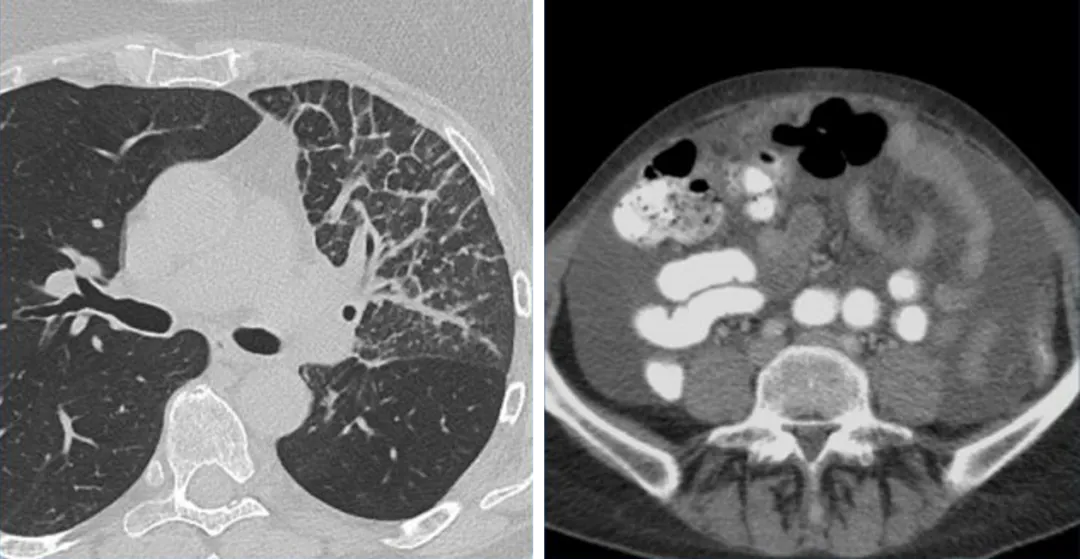

不可测量的病变

癌性淋巴管炎(左)和腹水(右)均属于不可测量病变,一般记录为非靶病灶,并在后续访视中判断是否存在或消失。

骨转移

在整个访视期间,骨转移的外观一般会发生改变,但大小通常保持不变,因此骨转移通常被认为是不可测量的病变。根据RECIST1.1,只有具有可识别的软组织成分的溶骨性病灶或混合性溶骨性病灶才能被视为是可测量病变。

一名80岁男性患者CT图像(左),非小细胞肺癌并成骨性骨转移,这种病变属于不不可测量病变。另一名69岁女性患者CT图像(右),右髂骨发生溶骨性转移,这种病灶属于可测量病灶,可以选作靶病灶。

一名34岁女性患有卵巢癌粟粒性肺转移,胸部CT肺窗的MIP图像显示肺内多发转移瘤,

但病灶都太小不能选作靶病灶,可以记录为一个非靶病灶组来评估。